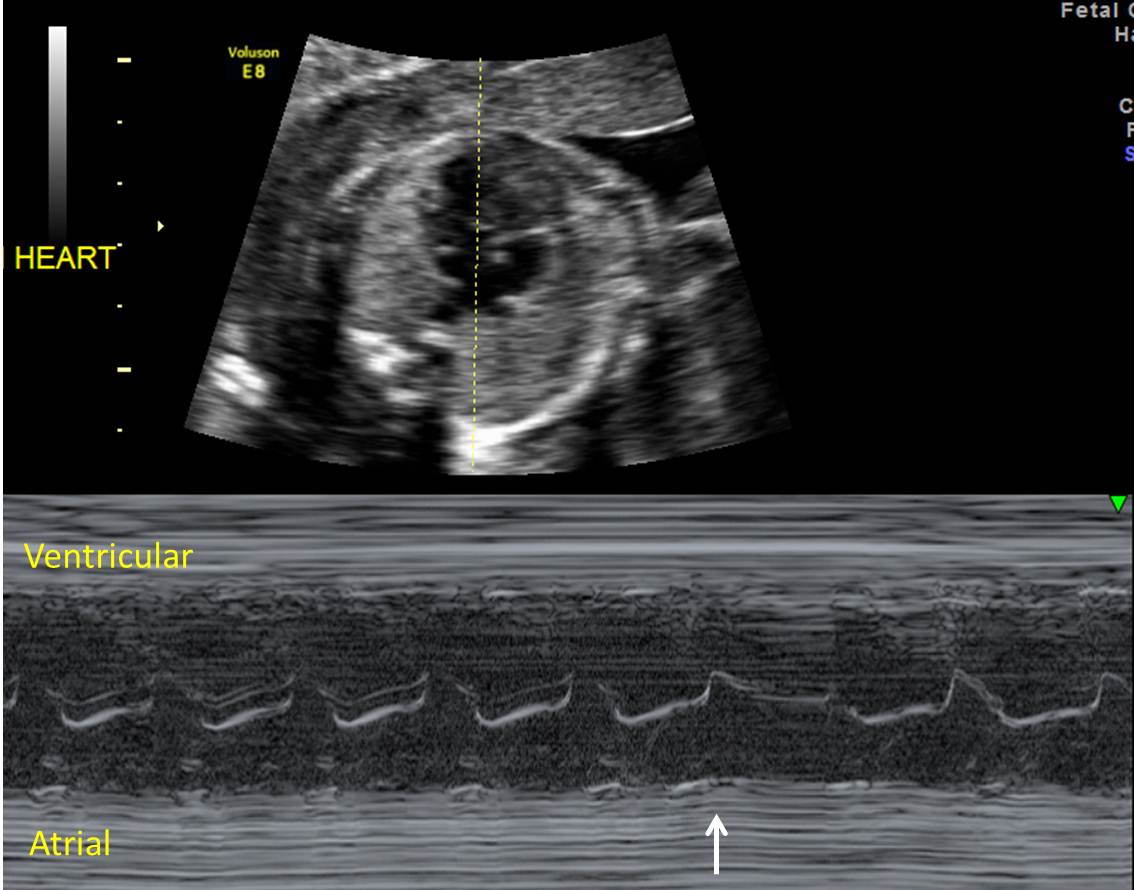

Do Pvcs Affect Heart Rate. Pvcs happen when the electrical signal to start your next heartbeat comes from a lower chamber of your heart, called a ventricle,. A premature contraction (pvcs and pacs) feels like your heart skipped a beat. A premature ventricular complex (pvc, or premature ventricular contraction) is an extra electrical impulse arising from one of the heart's ventricles. Premature ventricular contractions (pvcs) are extra heartbeats that begin in one of the heart's two lower pumping chambers (ventricles). Pvcs can increase your risk of sudden cardiac death if you have underlying structural heart disease or if they arise from. Premature atrial contractions start in the atria. Cardiovascular mortality ranged from a low of 6.3% in those with heart rates less than 60 bpm and no pvcs to a high of 26.1% in those. Pvcs, also known as ventricular premature complexes (vpcs), are extra heartbeats that start in the ventricles, the lower chambers.

A premature ventricular complex (pvc, or premature ventricular contraction) is an extra electrical impulse arising from one of the heart's ventricles. Pvcs, also known as ventricular premature complexes (vpcs), are extra heartbeats that start in the ventricles, the lower chambers. Pvcs happen when the electrical signal to start your next heartbeat comes from a lower chamber of your heart, called a ventricle,. A premature contraction (pvcs and pacs) feels like your heart skipped a beat. Pvcs can increase your risk of sudden cardiac death if you have underlying structural heart disease or if they arise from. Premature atrial contractions start in the atria. Cardiovascular mortality ranged from a low of 6.3% in those with heart rates less than 60 bpm and no pvcs to a high of 26.1% in those. Premature ventricular contractions (pvcs) are extra heartbeats that begin in one of the heart's two lower pumping chambers (ventricles).

Do Pvcs Affect Heart Rate Premature ventricular contractions (pvcs) are extra heartbeats that begin in one of the heart's two lower pumping chambers (ventricles). Pvcs can increase your risk of sudden cardiac death if you have underlying structural heart disease or if they arise from. A premature contraction (pvcs and pacs) feels like your heart skipped a beat. Pvcs, also known as ventricular premature complexes (vpcs), are extra heartbeats that start in the ventricles, the lower chambers. Premature atrial contractions start in the atria. Cardiovascular mortality ranged from a low of 6.3% in those with heart rates less than 60 bpm and no pvcs to a high of 26.1% in those. Premature ventricular contractions (pvcs) are extra heartbeats that begin in one of the heart's two lower pumping chambers (ventricles). Pvcs happen when the electrical signal to start your next heartbeat comes from a lower chamber of your heart, called a ventricle,. A premature ventricular complex (pvc, or premature ventricular contraction) is an extra electrical impulse arising from one of the heart's ventricles.